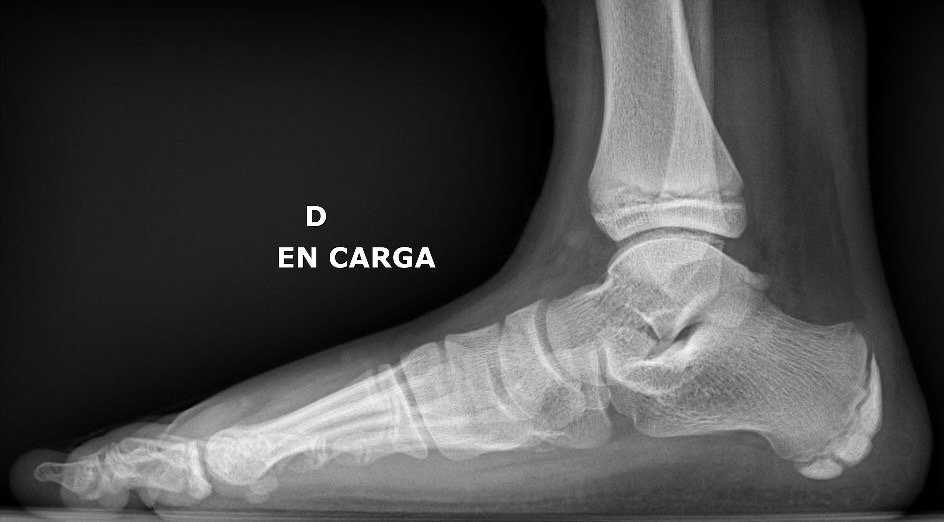

¿Cómo se diagnostica?

Es sencillo y no es necesario radiar al niño, ya que tendrá entre 8 y 13 años cuando sufra este dolor y es mejor evitar radiaciones, a menos que sea necesario o el dolor venga por un impacto, para descartar alguna fractura.